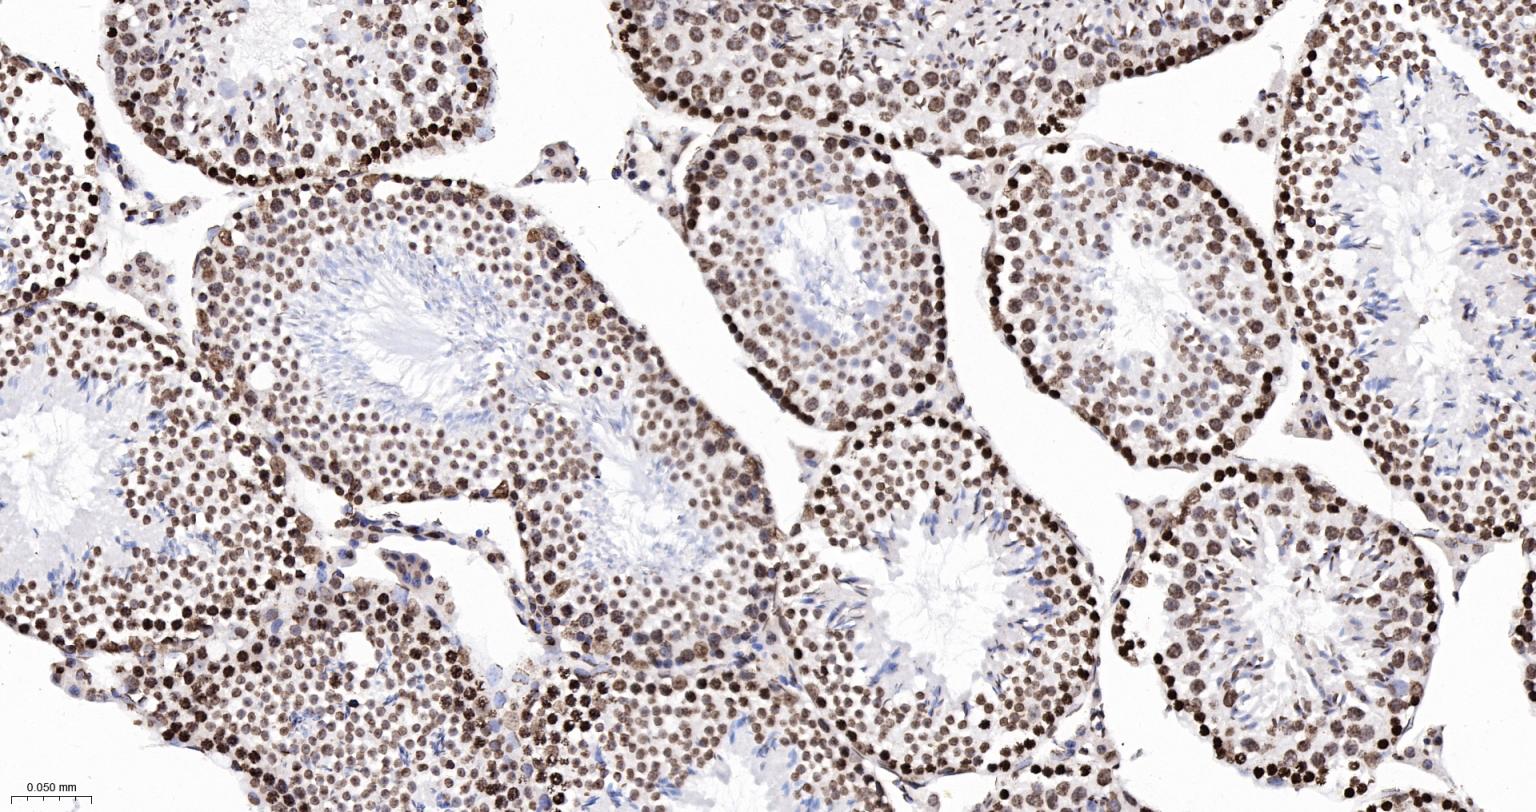

Paraformaldehyde-fixed, paraffin embedded Rat Testicles; Antigen retrieval by boiling in sodium citrate buffer (pH6.0) for 15 min; The section was incubated with phospho-SMC1 alpha (Ser957) Monoclonal Antibody, Unconjugated (bsm-62980R) at 1:200 overnight at 4°C, followed by conjugation to the bs-0295G-HRP and DAB (C-0010) staining.